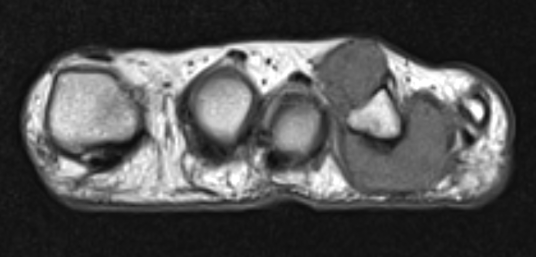

GCT flexor tendon sheath

GCT of tibialis posterior tendon sheath